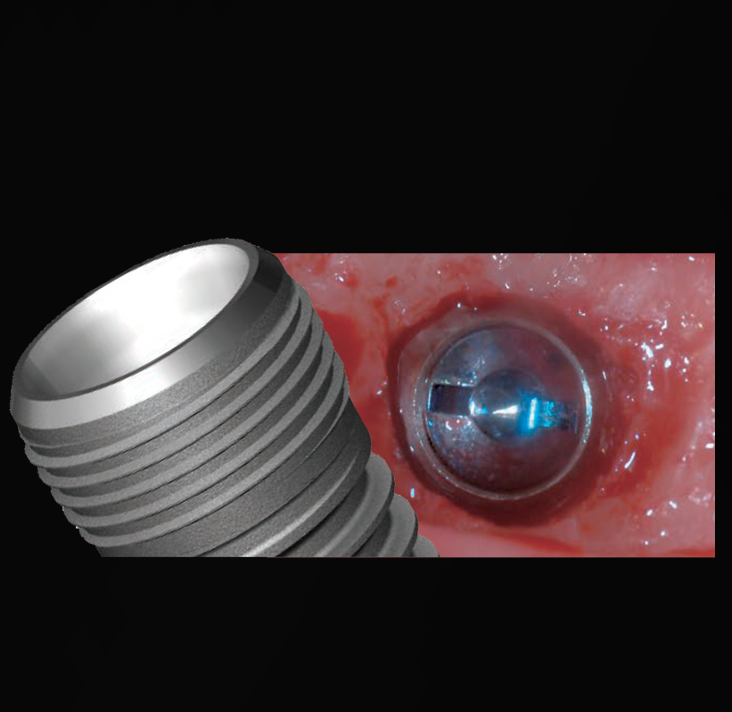

Protective Bevel DesignThe tapered bevel platform minimizes bacterial

infiltration and may eliminate the need

for bone profiling during surgery.